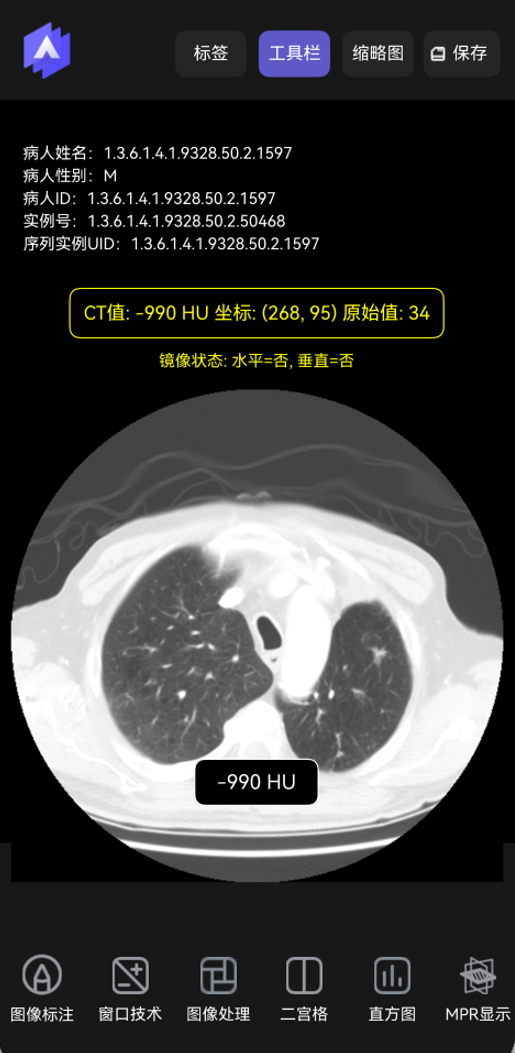

显示CT值。点击图像某个部位时在底部显示当前的CT值,如下图所示。